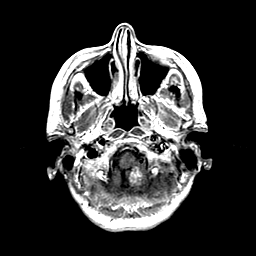

Metastatic Adenocarcinoma of the Colon: T1-weighted MR -- Slice #3

[Home][Help][Clinical] Slice 3